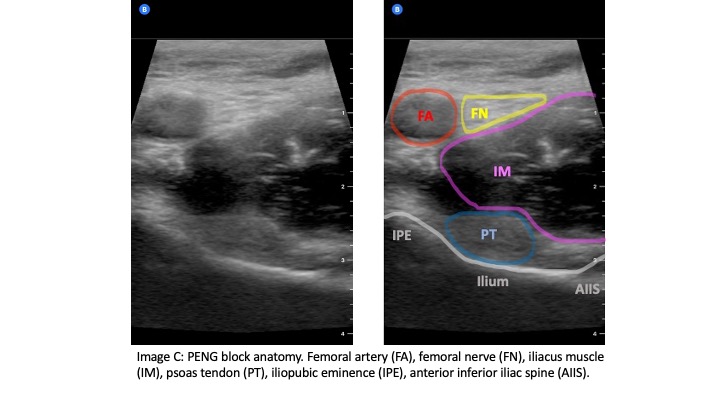

The FN, ON and AON arise from the lumbar plexus (L2-L4). The FN passes into the thigh lateral to the femoral artery under the inguinal ligament (IL) and gives off high (branchpoint proximal to the IL) and low (branchpoint distal to the IL) articular branches, both of which provide the majority of the sensory innervations to the lateral and superomedial hip joint capsule. The obturator nerve passes through the obturator foramen and also gives off high (branchpoint within the obturator canal) and low (branchpoint distal to the obturator canal) articular branches which provide sensory innervation to the inferomedial hip joint capsule. The AON is present in about 30% of cases and arises from L3-L4.3 It descends medial to the psoas muscle, passes underneath the IL, and then dives underneath the pectineus muscle. Cadaver studies have shown that the articular branches of the FN, ON, and AON lie in the subfascial plane between the psoas tendon and the ilium and course downward into the hip joint between the iliopubic eminence (IPE) medially and the anterior inferior iliac spine (AIIS) laterally (Image A).4 Using these landmarks, a bolus of at least 20 CCs of subfascial local anesthetic can be injected to anesthetize these nerve fibers as they enter the hip capsule.5

The curvilinear probe is used at an oblique angle parallel to the IL with probe marker to the patient's right side. The linear probe may be used in patients who are thin for better image resolution. Initially, the probe should be positioned inferior to the IL to identify the femoral head (Image B). Then the probe can be moved cranially until the anterior inferior iliac spine (AIIS) and iliopubic eminence (IPE) of the ilium are visualized (Image C). The femoral artery, femoral nerve, iliacus muscle and psoas tendon should be identified. The femoral nerve generally lies right above the psoas tendon on top of the iliacus muscle and is just lateral to the femoral artery. The target is the subfascial plane located underneath the psoas tendon and above the ilium. A 20G or larger long spinal needle or echogenic nerve block needle is inserted in a lateral-to-medial approach until contact with the ilium is made underneath the psoas tendon (Image D). Hydrodissection of the fascial plane using saline initially helps to visualize the correct location before injecting 20 CCs of long-acting anesthetic, such as ropivacaine or bupivacaine with epinephrine. The block has been shown to be effective with a lower concentration of local anesthetic such as 0.25% bupivacaine with epinephrine.